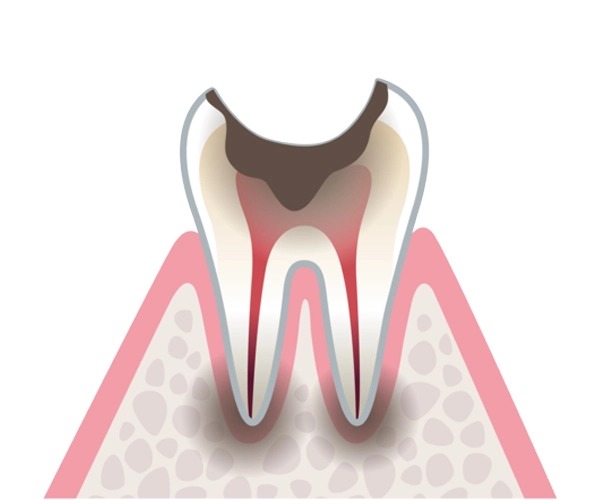

むし歯の進行

歯の表面がむし歯に侵された状態。痛みなどの自覚症状はないですが、歯の表面に着色が見られたり、色つやが失われたりしています。

歯の内側の象牙質まで達して、歯に穴が開いた状態。冷たいものがしみたり、噛んだときに痛みを感じたりします。

歯の神経まで達して、歯に大きな穴が開いた状態。熱いものがしみたり、何もしなくても痛みを感じたりするようになります。

歯ぐきから上がほとんど崩壊、歯の根っこだけが残った状態。こうなると歯の温存は難しく、抜歯を検討しなければなりません。